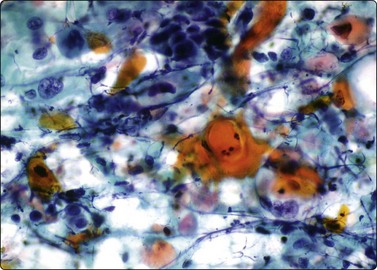

image

Fig. 6.41 Cystic papillary carcinoma

Cystic change in metastatic papillary carcinoma in cervical lymph node; mainly foamy cells with some pigment resembling macrophages; one cluster of degenerate atypical epithelial cells (MGG, HP).

Fluid aspirated from cystic PC is uncharacteristic, brown or resembles altered blood. The diagnosis can easily be missed if well-preserved epithelial cells are scarce (Fig. 6.41).30,31,71 Presence of numerous macrophages, with many in cohesive clusters, should raise a suspicion of PC. Some of these cells are probably degenerating tumor cells exfoliated from the cyst lining (Fig. 6.42). They may represent foam cell metaplasia in tumor cells, and careful scrutiny will usually reveal nuclear features of PC. Large cell size, pseudoinclusions, nuclear grooves, and multiple well-defined vacuoles in atypical histiocytoid cells favor a diagnosis of PC.186